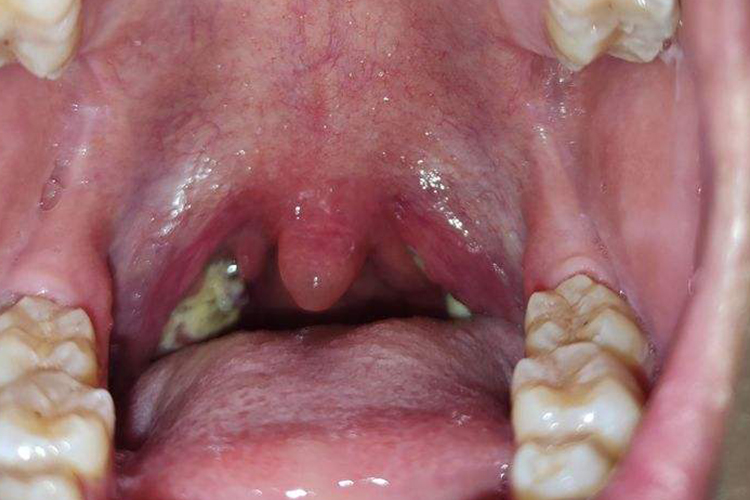

化脓性扁桃体炎:起病急,表现为高热,咽痛,口臭等症状,严重时可见腺样

嗓子发炎化脓图

疱疹性咽炎咽喉红肿有白色溃疡图

急性滤泡性扁桃体炎扁桃体症状图